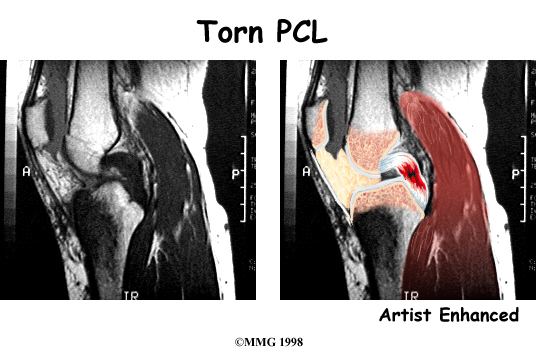

The magnetic resonance imaging (MRI) scan is probably the most accurate test without actually looking into the knee. The MRI machine uses magnetic waves rather than X-rays to show the soft tissues of the body. This machine creates pictures that look like slices of the knee. The pictures show the anatomy, and any injuries, very clearly. This test does not require any needles or special dye and is painless.

Ruptured PCL

The PCL is the primary stabilizer of the knee and the main controller of how far backward the tibia moves under the femur. This motion is called posterior translation of the tibia. If the tibia moves too far back, the PCL can rupture.